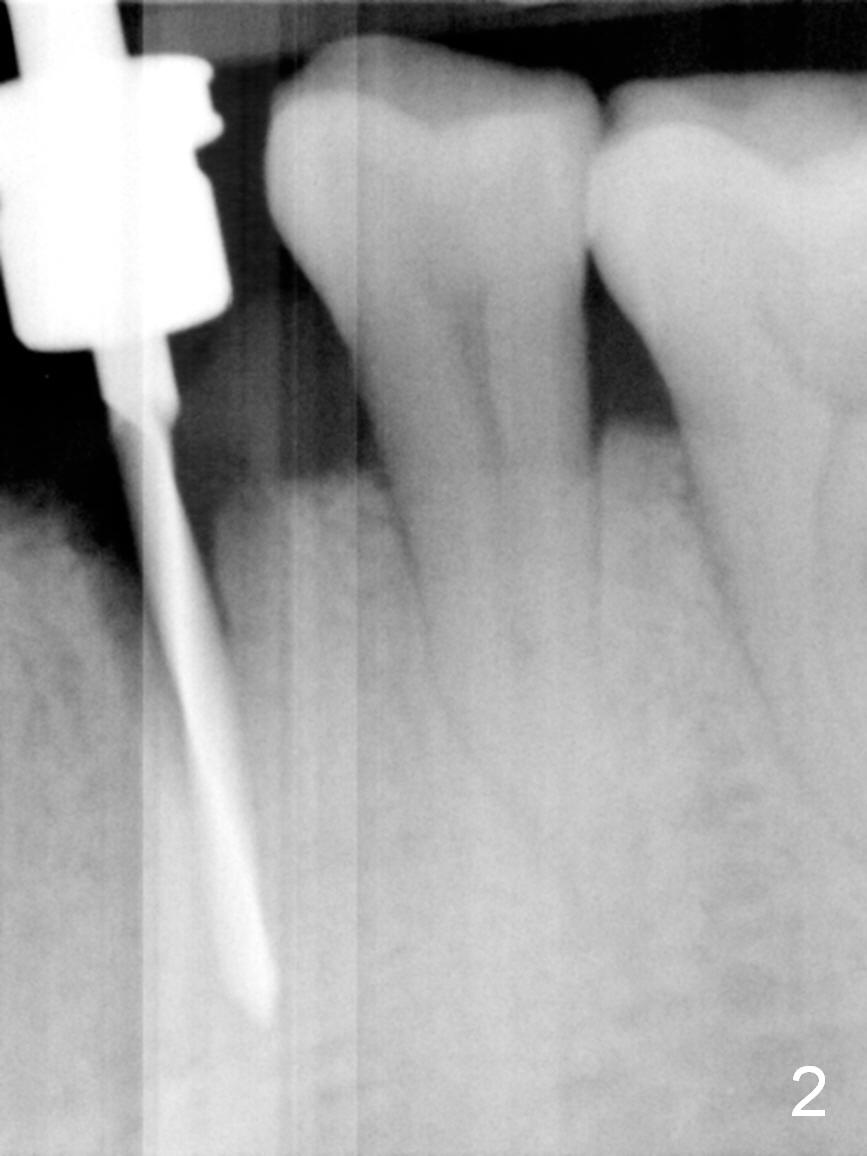

The residual root at #21 seems to be buccally positioned (Fig.1 *). The initial osteotomy is established with the 1.6 mm drill at 11 mm (Fig.2). Later the depth increases to 13 mm. The initial osteotomy is found to be too lingual, but experience shows that as osteotomy increases in diameter, the trajectory would shift buccally due to the thick lingual plate (slope). When 3.3 mm Magic drill reaches 11 mm, the patient feels pain. It is probably due to the dense bone. A 4x11 mm IBS implant cannot be seated due to high torque; it is removed. The osteotomy is increased with 3.8 mm drill. The implant is re-seated with >55 Ncm; it is over-lingually placed. Due to failure to seat the implant driver completely, the implant cannot be un-torqued. A 4.5 mm 15° angled abutment (3 mm cuff) is placed for immediate provisional (Fig.3,4 *).